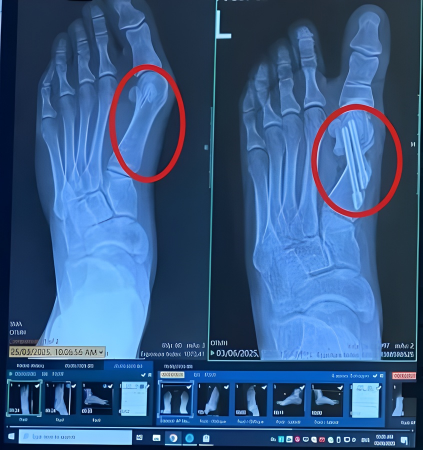

That painful bump isn’t “extra bone.”

It forms because your big toe is being pushed out of its natural alignment — drifting inward and forcing the joint to stick outward.

In many cases, when this deformity becomes more severe, people are told that the only solution is to cut the bone and surgically realign the toe.

🦶 The real problem is misalignment — not something that needs to be removed.

Why Bunion Surgery Often Fails

Bunion surgery has a 30–50% failure rate, often leading to joint stiffness, scarring, or pain returning shortly after recovery.

Surgery doesn’t fix the root cause.

It simply cuts the bone and screws the joint back in place, but it doesn’t correct the muscle imbalance and misalignment that caused the bunion in the first place.